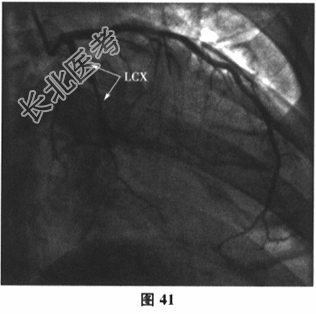

- 多项选择题6.[提示]运动负荷心电图试验示:最大运动功量3.3METs, Ⅱ、Ⅲ、aVF、V3~V4导联ST段压低0.05~0.1mV(图38)。查血小板聚集率:Ara14.57%, ADP36.55%。再次行冠状动脉造影:回旋支近端次全闭塞, LCX内支架内膜重度增生;LAD中段斑块浸润, 最重狭窄30%~40%,轻度肌桥压迫, 第二对角支狭窄70%;RCA近段斑块浸润, 如图39~图41所示。故于回旋支再次植入一枚支架(Promus Element2.75mm×38mm),如图42所示。